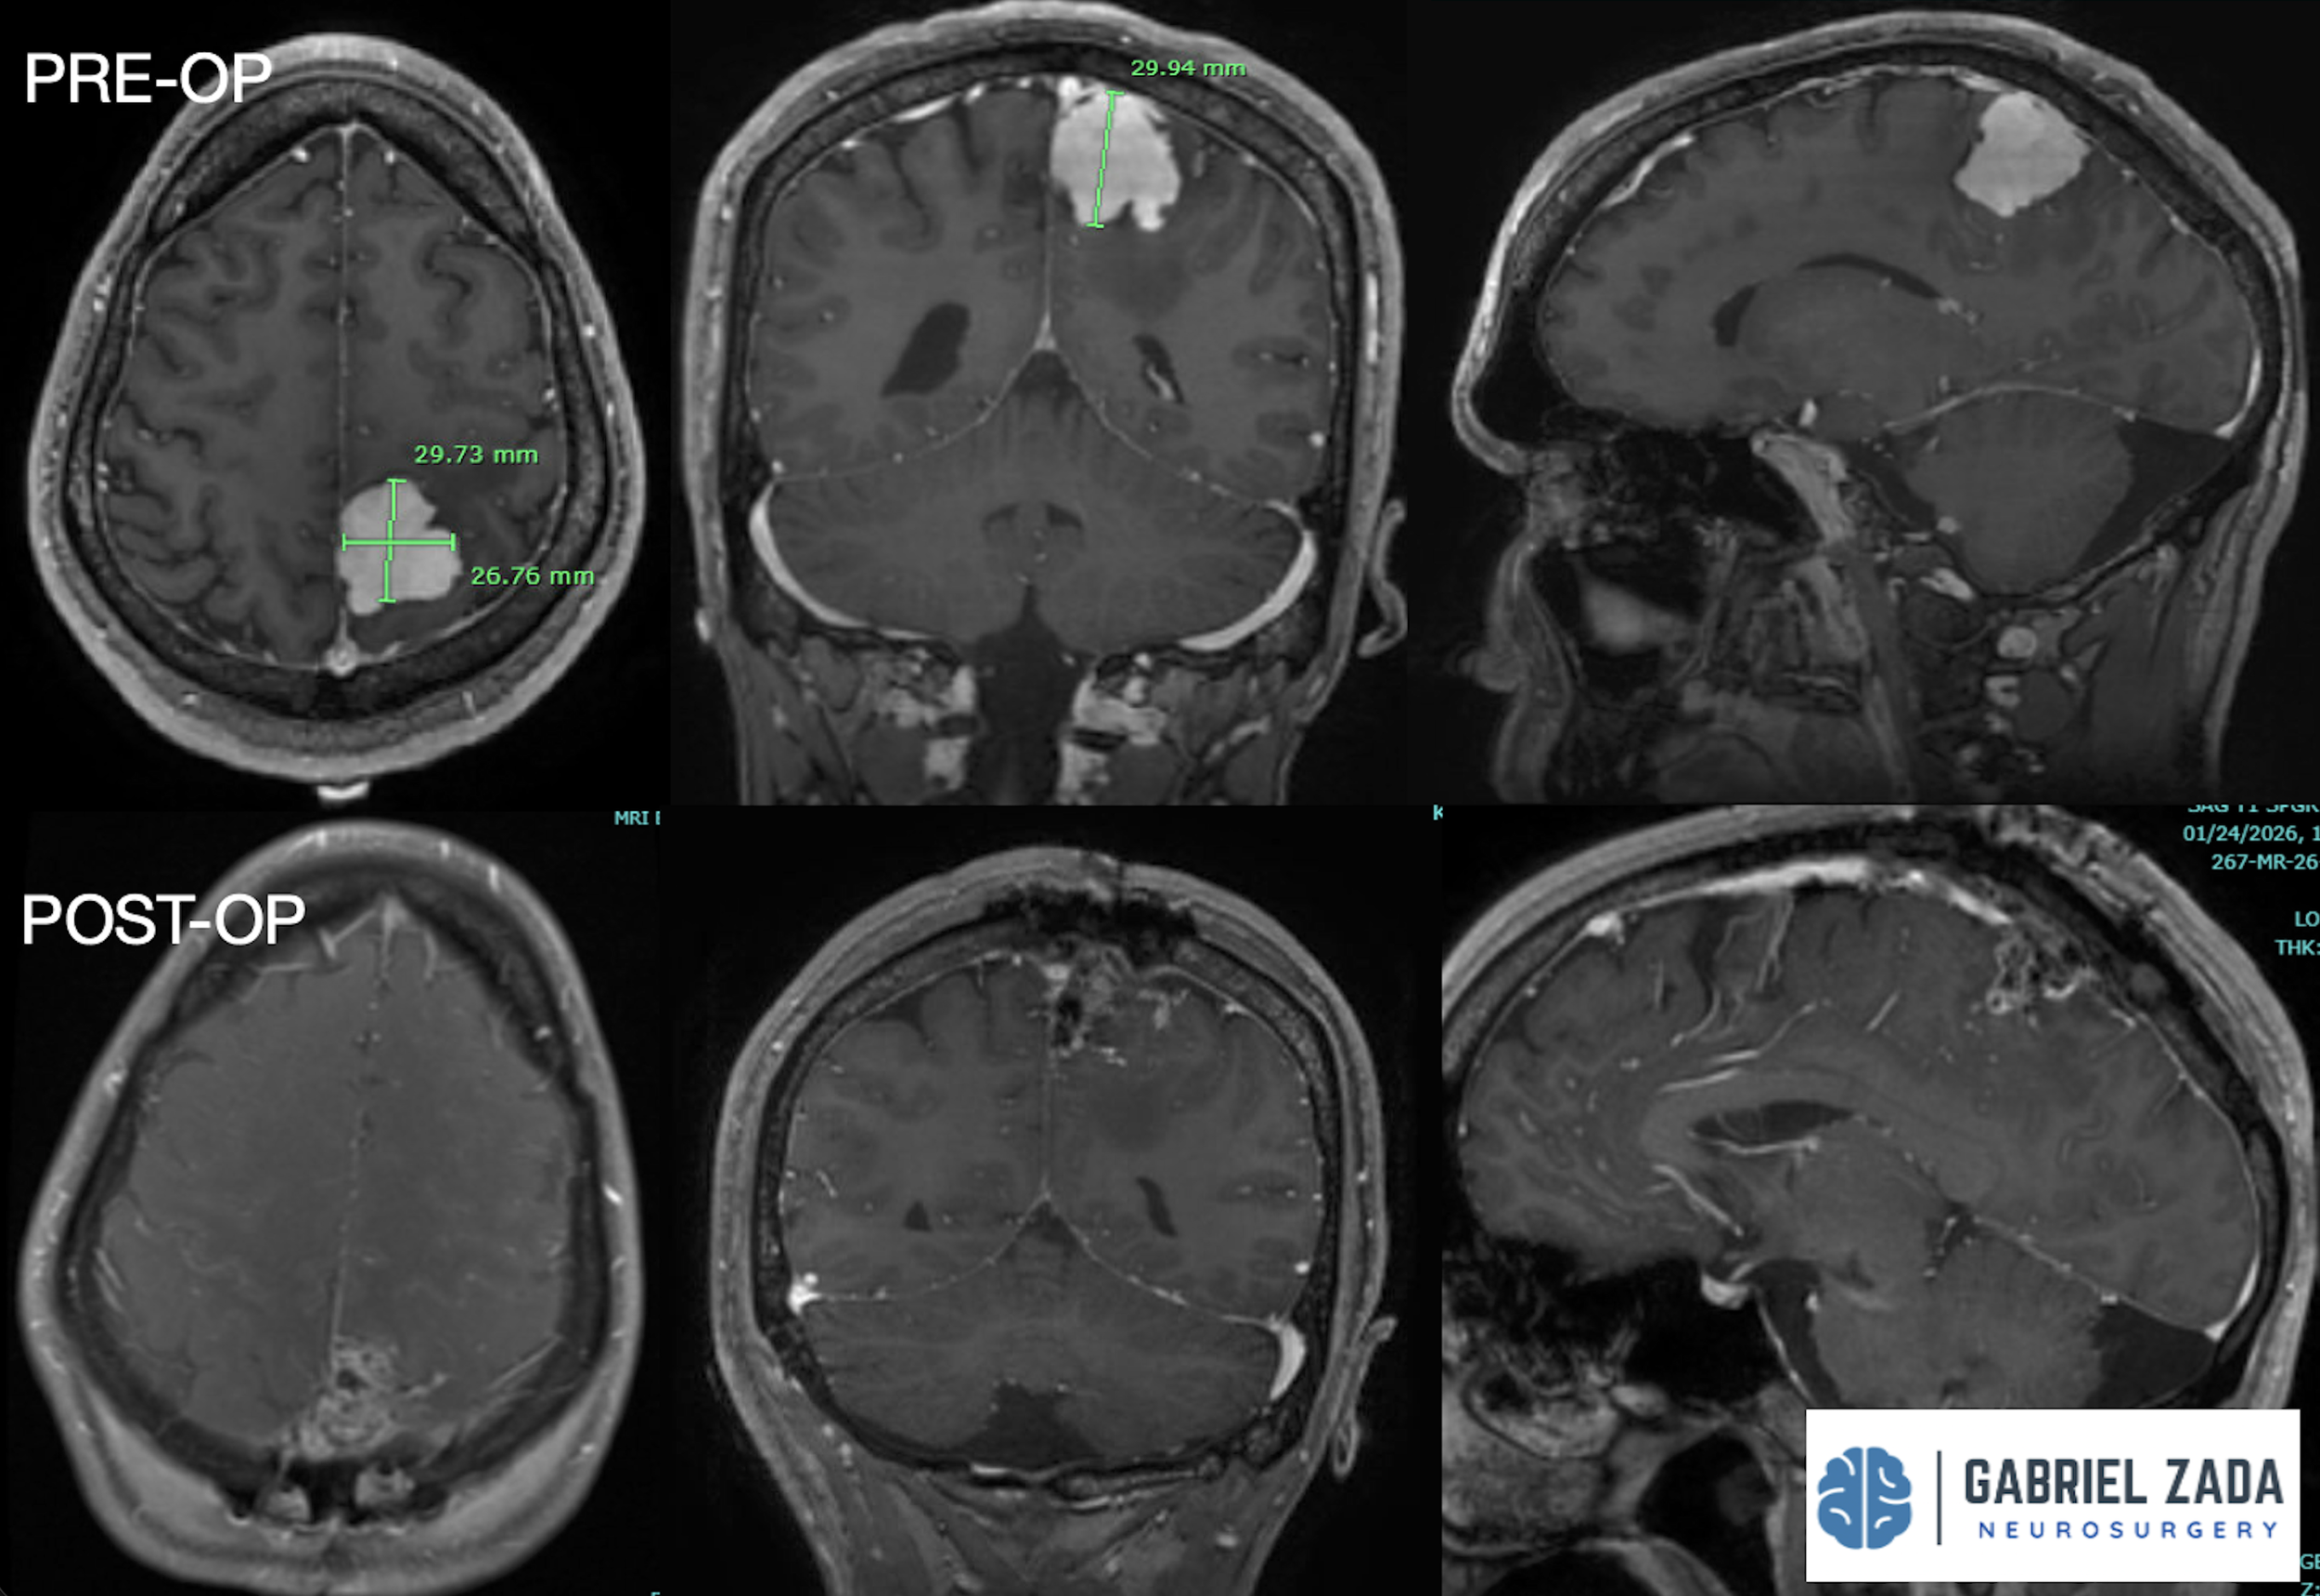

Explore this comprehensive gallery featuring pre‑ and post‑operative imaging of patients with skull‑base tumors treated by Gabriel Zada, MD, MS, FAANS, FACS. These cases highlight Dr. Zada’s expertise in advanced neurosurgical techniques and outcomes.

*Representative cases shown for educational purposes. All images de-identified. Individual results vary.